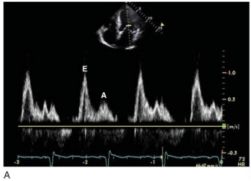

159.參考圖 A, B, C, 請問下列敘述何者錯誤?

(A) 此疾病早期 (early stage),還保有左心室收縮功能。 (B) 此疾病,左心室舒張末期壓力上升,影響左心房收縮血液至左心室,因此二尖瓣血 流 (mitral flow) 之 A 波通常變小。 (C) 此疾病,左心房壓力上升,影響肺靜脈血流 (pulmonary vein flow),造成肺靜脈血流 之流速在收縮期時 (S) 降低。 (D) 由於全面舒張期異常,因此,tissue Doppler 在二尖瓣環狀 (mitral annulus) 之 E’流 速通常小於 7 cm/sec。 (E) 此疾病主要是因為心包膜異常變厚,或是發炎,或是鈣化,而導致舒張期填充 (diastolic filling) 異常。